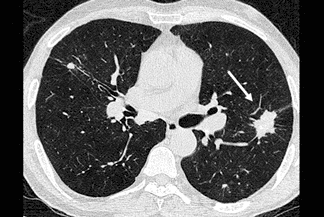

Texto alternativo para a imagem Figura 2 - Créditos: Dra Elazir Mota - Rio de Janeiro/RJ

Descrição da lesão: Tomografia computadorizada de tórax sem a administração do contraste. Grandes opacidades nas regiões posteriores dos lobos superiores, associadas à distorção arquitetural do parênquima. Observam-se ainda calcificações no interior das opacidades pulmonares (setas brancas - figuras 1 e 2).